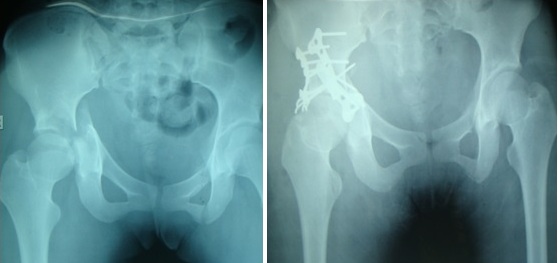

Hình 1: Bệnh nhân Nguyễn Thị T.: kết quả điều trị

Số lượng nẹp cố định xương tùy theo mức độ vững chắc sau khi nắn, không nhất thiết phải dùng nhiều nẹp trong các trường hợp vỡ phức tạp. X-quang sau mổ cho thấy có 9/17 trường hợp được nắn hoàn hảo không còn di lệch sau mổ, 8 trường hợp còn lại chỉ còn di lệch từ 2-3mm, nhưng mặt khớp vẫn được nắn chỉnh tốt.